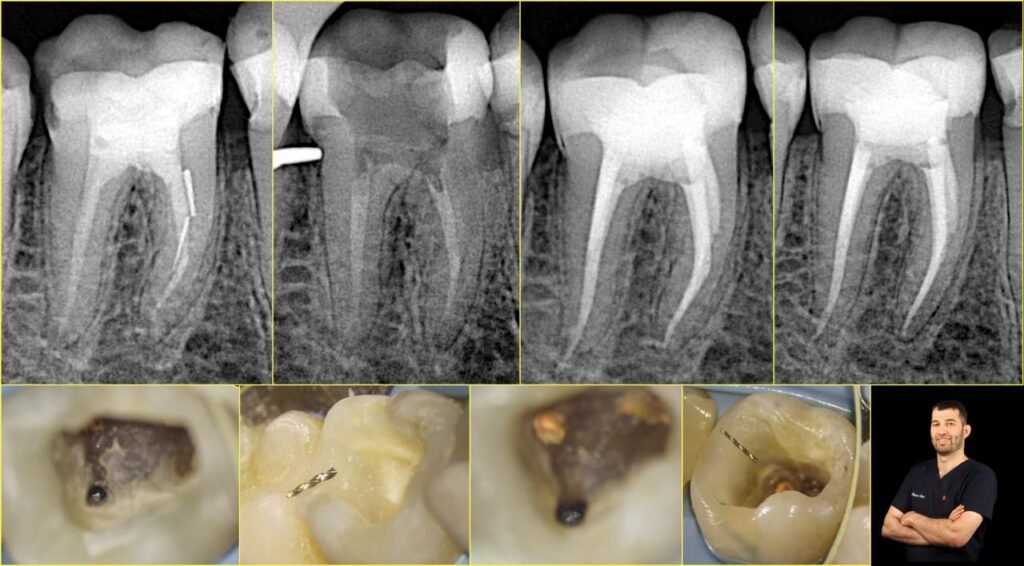

The patient was referred with ongoing symptoms, and radiographic examination clearly showed inadequate obturation and two separated files lodged in the mesial canals.

Dr. Alani utilized the ROGIN UltraMax Ultrasonic Activator to safely loosen and retrieve both separated files one by one. The ultrasonic vibration effectively transmitted energy to dislodge the fragments without excessive dentin removal or risk of further complications. Both files were successfully removed, as documented in the intraoperative photographs.

The final postoperative radiograph confirmed a well-obturated root canal system with proper coronal restoration.

At the one-year recall, the patient was completely symptom-free with no signs of tenderness or pain. Radiographic evaluation showed healthy periapical tissues, confirming the long-term success of the retreatment.